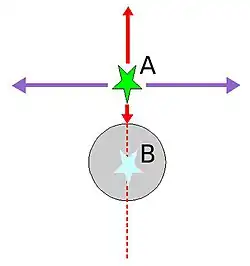

Erläuterung

Man stelle sich eine Nuklidanreicherung vor, die sich in der Nähe eines wassergefüllten Zylinders mit 30 cm Durchmesser befindet. Die dort zerfallenen Nuklide senden ihre Vernichtungsstrahlung in alle Raumrichtungen aus. Es sollen zwei Fälle betrachtet werden: Fall 1: Die beiden entstandenen Photonen 1 und 2 fliegen exakt tangential von der Objektoberfläche weg (violette Pfeile), weder Photon 1 noch Photon 2 durchdringt irgendeinen Teil des Zylinders. Fall 2: Photon 1 zielt radial in Richtung Zylindermitte. Naturgemäß entfernt sich Photon 2 vom Zylinder, ohne auch nur einen Teil des Zylinders zu durchdringen (nach oben weisender roter Pfeil). Die Wahrscheinlichkeit ist groß, dass Photon 1 beim Durchlauf von 30 cm Wasser absorbiert und damit Photon 2 zu einem „Single“ wird und damit für die Bildrekonstruktion nicht mehr zur Verfügung steht.

Würde die Absorption der Strahlung bei der Bildrekonstruktion unberücksichtigt gelassen, wären Artefakte die Folge; die gemessene Aktivitätsverteilung stimmte ohne Absorptionskorrektur nicht mit der tatsächlichen Verteilung überein.

Relevanz für die Quantifizierung von Anreicherungen

Die Wahrscheinlichkeit einer Absorption ist im Fall 2 (rote Pfeile) unabhängig davon, ob die Annihilation an der Oberfläche (Ort A) oder in der Mitte des Objektes (Ort B) stattfand. Bei Annihilation an der Oberfläche (Ort A) durchläuft Photon 1 den gesamten Zylinder, Photon 2 nur Luft, bei Annihilation in der Zylindermitte (Ort B) durchlaufen beide Photonen den halben Zylinder, was zur selben Absorptionswahrscheinlichkeit führt. Da die Absorptionswahrscheinlichkeit somit nur von der Gesamtschwächung des durchstrahlten Volumens, nicht jedoch vom Ort der Annihilation auf der Koinzidenzlinie abhängt, ermöglicht dies eine tiefenunabhängige Quantifizierung der Nuklidanreicherung.